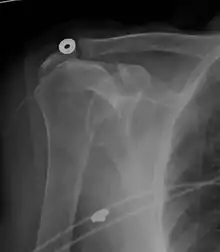

A complete tear of the supraspinatus resulting in a shift upwards of the head of the humerus

Projectional radiograph of normal glenohumeral position.[52]

High-riding humeral head in a rotator cuff tear.

X-ray projectional radiography cannot directly reveal tears of the rotator cuff, a 'soft tissue', and consequently, normal X-rays cannot exclude a damaged cuff. However, indirect evidence of pathology may be seen in instances where one or more of the tendons has undergone degenerative calcification (calcific tendinitis). The humeral head may migrate upward (high-riding humeral head) secondary to tears of the infraspinatus, or combined tears of the supraspinatus and infraspinatus.[52] The migration can be measured by the distance between:

• A line crossing the center of a line between the superior and inferior rims of the glenoid articular surface (blue in image).

• The center of a "best-fit" circle positioned over the humeral articular surface (green in image)

Normally, the former is positioned inferiorly to the latter, and a reversal therefore indicates a rotator cuff tear.[52] Prolonged contact between a high-riding humeral head and the acromion above it may lead to X-ray findings of wear on the humeral head and acromion; secondary degenerative arthritis of the glenohumeral joint (the ball and socket joint of the shoulder), called cuff arthropathy, may follow.[51] Incidental X-ray findings of bone spurs at the adjacent acromioclavicular joint may show a bone spur growing from the outer edge of the clavicle downward toward the rotator cuff. Spurs may also be seen on the underside of the acromion, once thought to cause direct fraying of the rotator cuff from contact friction, a concept currently regarded as controversial.